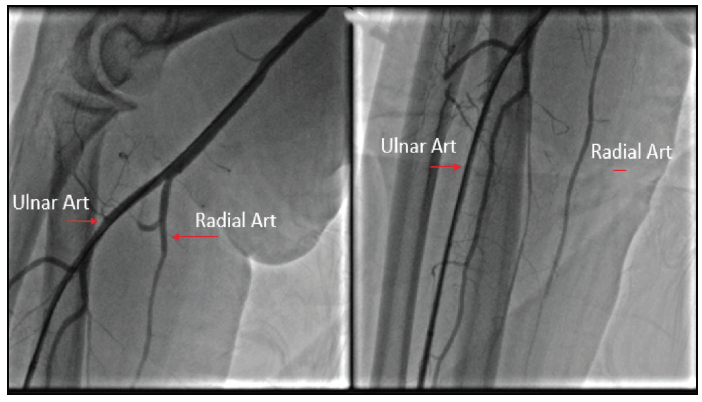

Another example of using TUA includes a patient who underwent a valve-in-mitral annular calcification transcatheter mitral valve replacement utilizing a 29-mm Sapien 3 valve (Edwards Lifesciences) for severe degenerative mitral stenosis. The patient required an alcohol septal ablation days later to reduce the left ventricular outflow gradient. The radial artery was palpated and found to be very small. As illustrated in the forearm angiogram (Figure 1), the ulnar artery was larger. The ulnar artery was used to successfully perform the procedure with no complications, illustrating that the ulnar artery is a safe and feasible alternative to an inadequate radial artery.